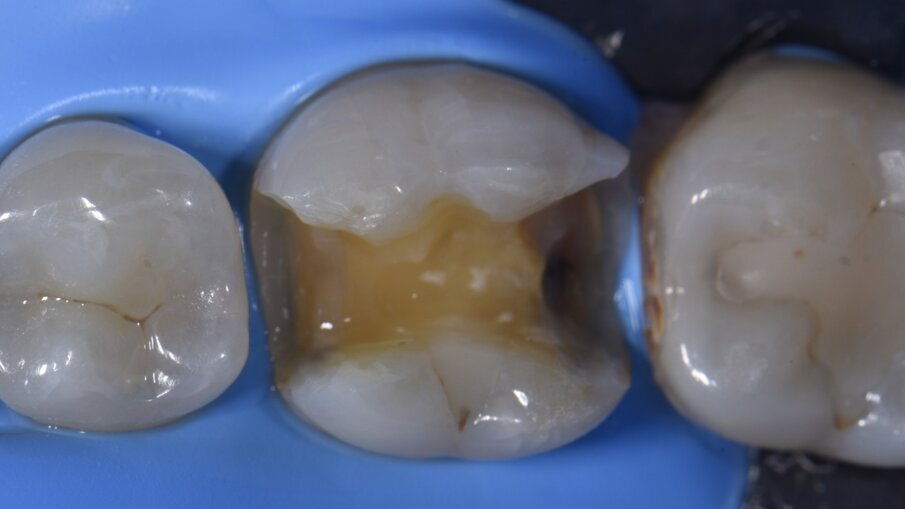

Un fallimento parziale del trattamento è stato diagnosticato sul dente 19 rispetto a un precedente restauro in composito (Fig. 1). Il paziente da un mese si lamentava di una sensibilità al morso. Le preoccupazioni primarie riguardavano sia il micromovimento del vecchio restauro, ma anche la possibile presenza di fratture o microfratture, che potevano essere chiarite solo tramite un restauro esplorativo.

Il paziente è stato anestetizzato utilizzando una Lidocaina al 2% con epinefrina 1:100.000, dopodiché è stata posizionata una diga di gomma (NicTone). Eseguita la preparazione, il restauro è stato rimosso insieme a praticamente tutta la linea sottostante per permettere la valutazione del pavimento pulpare. Non sono state identificate crepe o microfratture ed è stato utilizzato un rilevatore di carie (rilevatore di carie, Kuraray) per garantire gli endpoints di rimozione della carie (Fig. 2). I margini sono stati smussati (0,5-1,0 mm) poiché più il margine è vicino alla superficie della cavità dell’apice della cuspide, più si tenterà di legarsi lateralmente ai prismi di smalto, mentre è più efficace legarsi alle estremità. La smussatura consente l’esposizione trasversale dei prismi e una migliore efficienza di mordenzatura e adesione. La microabrasione ad aria è stata eseguita isolando il dente adiacente con una striscia di metallo seghettato e utilizzando ossido di alluminio da 27 micron (Prep Start, Danville Engineering) a 2-3 bar di pressione. Questa operazione è stata completata prima del posizionamento di qualsiasi sistema di matrici sezionali poiché l’irruvidimento tipico della matrice unito all’uso di un adesivo automordenzante contenente 10-MDP (legami 10-MDP a metalli non preziosi) vedrà una rimozione della matrice più difficile dopo la costruzione della parete, spesso con residui del colore del rivestimento in Teflon della fascia lasciata aderente al restauro.